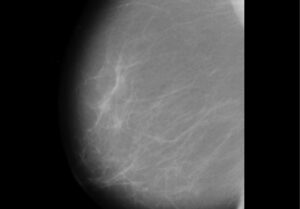

Les mamografies redueixen un 40% la possibilitat de morir per càncer de mama

La possibilitat de morir per un càncer de mama és un 40% inferior entre les [...]